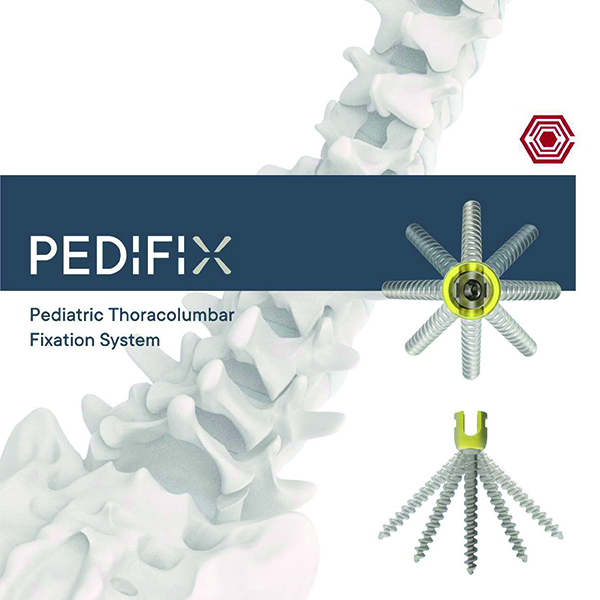

Pedifix

Akif Kaya Aybek

Norm Akademi

- Surgical Technique

- Implant Types

- Instrument Container

- Instrument Type